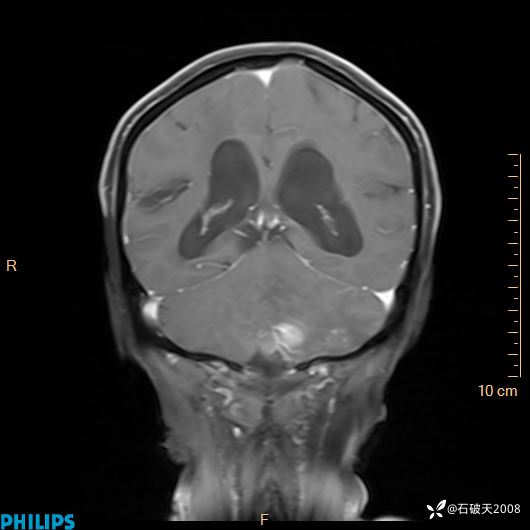

书上说这个肿瘤发生在幕下仅4.09%,你会想到它吗?(病理已公布)

女 86岁 主 诉:乏力1月

现病史:患者1月前活动出现双下肢乏力,无头晕、头痛、恶心、呕吐、肢体活动不利,休息后缓解,间断断发作,症状进行性加重,在家口服药物治疗(具体不详),效差,为进一步诊治,来我院,门诊按“乏力”收住我科,患者自发病以来,神志清,精神稍差,饮食睡眠欠佳,大小便正常,体重未见明显改变。

增强冠状位